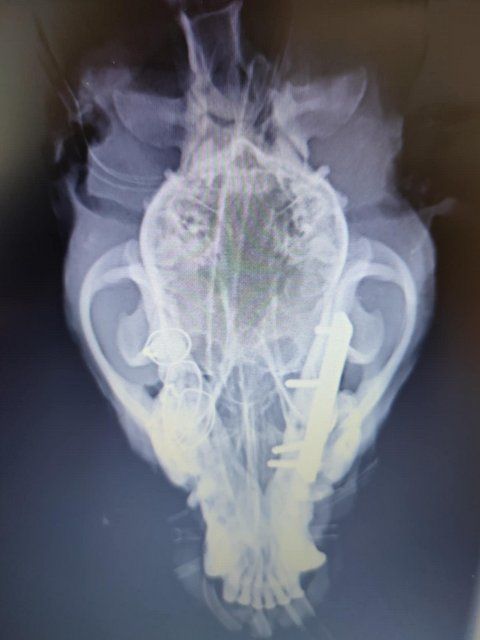

Röntgenbilder zeigten das Ausmaß der Zerstörung des Unterkiefers und den Bruch eines Beines.

Dieser Hund muss grausame Schmerzen haben, Zähne sind aus der Verankerung gerissen und sein Gesichtsschädel ist nicht mehr symmetrisch. Ein großes Stück des Unterkiefers ist komplett abgebrochen.

Es braucht sicher viel Geschick, um das wieder so zusammenzusetzen, dass der Hund später problemlos fressen kann.

Camush Kopf ist wieder symmetrisch, der Kiefer wird jetzt mit Platte und Verdrahtung zusammengehalten und ein paar Zähne fehlen jetzt.